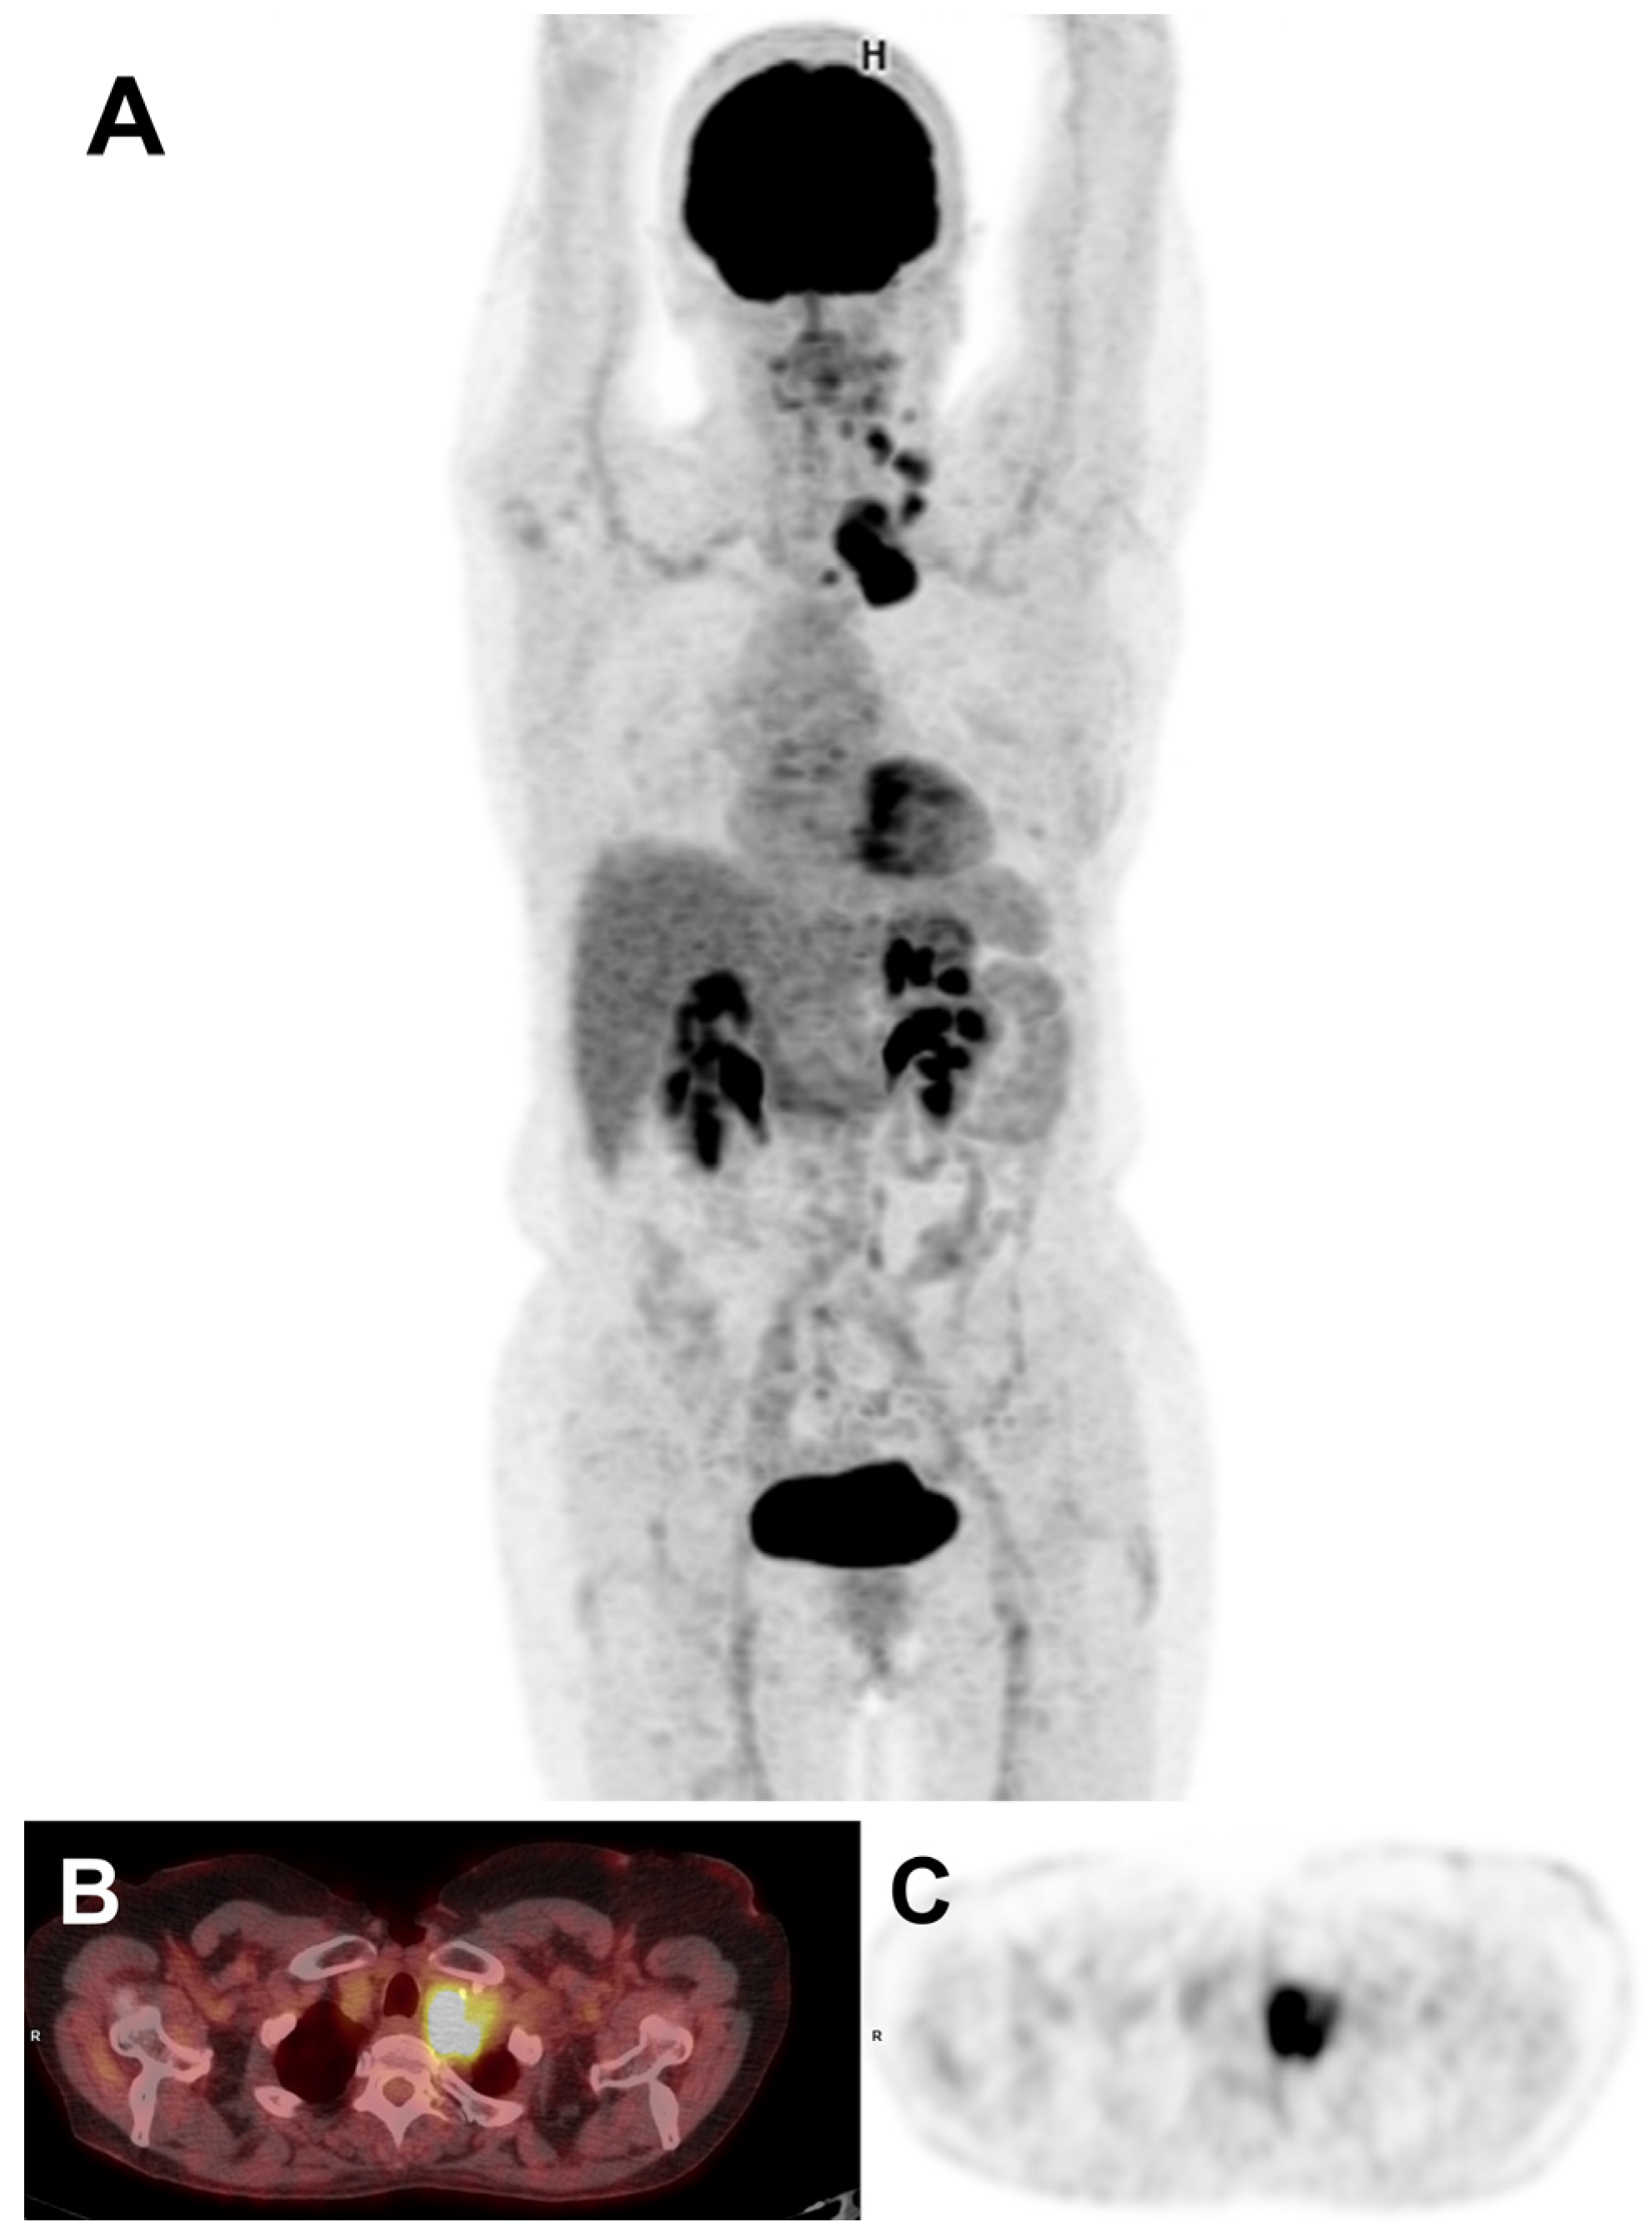

2. Case Presentation

- Balakirouchenane, D.; Seban, R.; Groussin, L.; Puszkiel, A.; Cottereau, A.S.; Clerc, J.; Vidal, M.; Goldwasser, F.; Arrondeau, J.; Blanchet, B.; et al. Pharmacokinetics/Pharmacodynamics of Dabrafenib and Trametinib for Redifferentiation and Treatment of Radioactive Iodine-Resistant Mutated Advanced Differentiated Thyroid Cancer. Thyroid Off. J. Am. Thyroid Assoc. 2023, 33, 1327–1338. [Google Scholar] [CrossRef]

- Rothenberg, S.M.; McFadden, D.G.; Palmer, E.L.; Daniels, G.H.; Wirth, L.J. Redifferentiation of Iodine-Refractory BRAF V600E-Mutant Metastatic Papillary Thyroid Cancer with Dabrafenib. Clin. Cancer Res. 2015, 21, 1028–1035. [Google Scholar] [CrossRef] [PubMed]

- Jaber, T.; Waguespack, S.G.; Cabanillas, M.E.; Elbanan, M.; Vu, T.; Dadu, R.; Sherman, S.I.; Amit, M.; Santos, E.B.; Zafereo, M.; et al. Targeted Therapy in Advanced Thyroid Cancer to Resensitize Tumors to Radioactive Iodine. J. Clin. Endocrinol. Metab. 2018, 103, 3698–3705. [Google Scholar] [CrossRef] [PubMed]